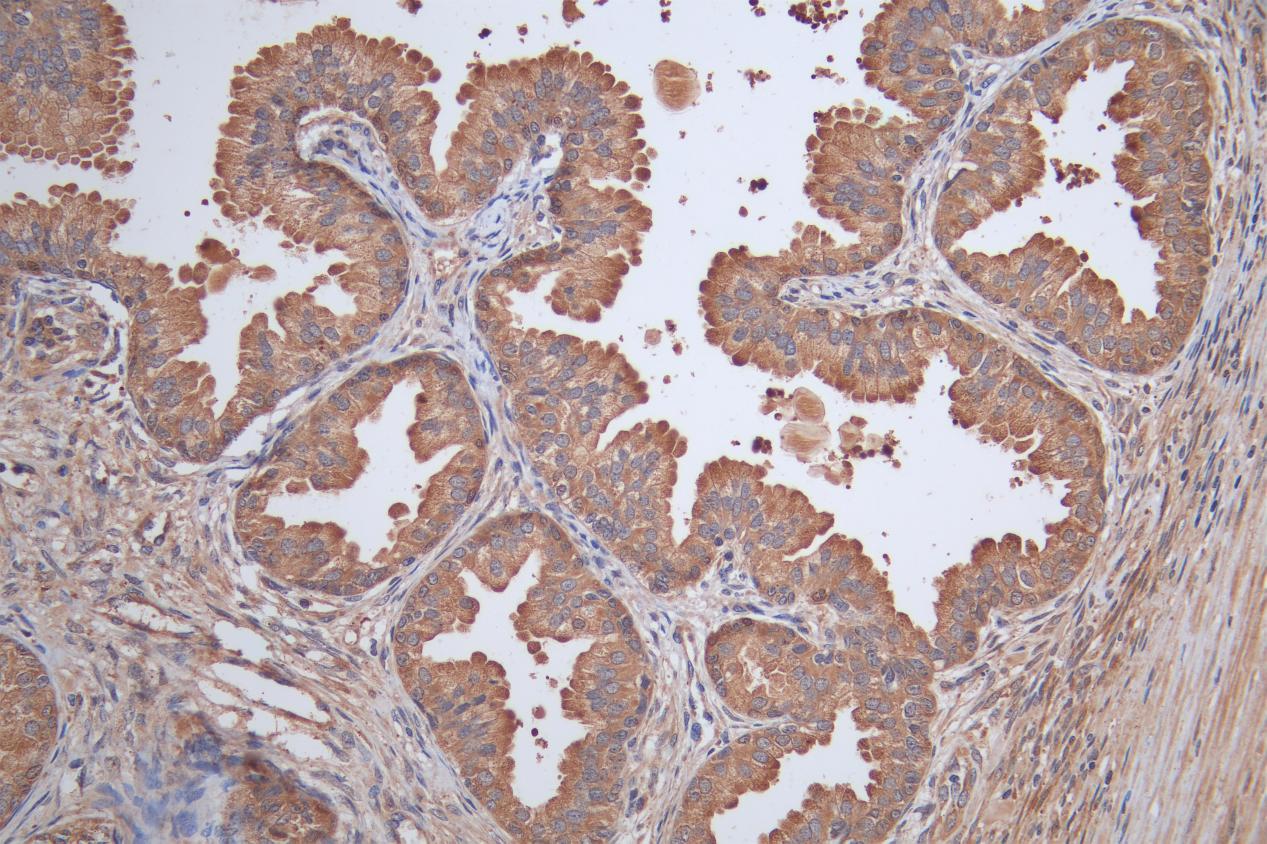

Immunohistochemistry image of CSB-PA621886ESR1HU diluted at 1:50 and staining in paraffin-embedded human prostate tissue performed on a Leica BondTM system. After dewaxing and hydration, antigen retrieval was mediated by high pressure in a citrate buffer (pH 6.0). Section was blocked with 10% normal goat serum 30min at RT. Then primary antibody (1% BSA) was incubated at 4°C overnight. The primary is detected by a Goat anti-rabbit polymer IgG labeled by HRP and visualized using 0.05% DAB.